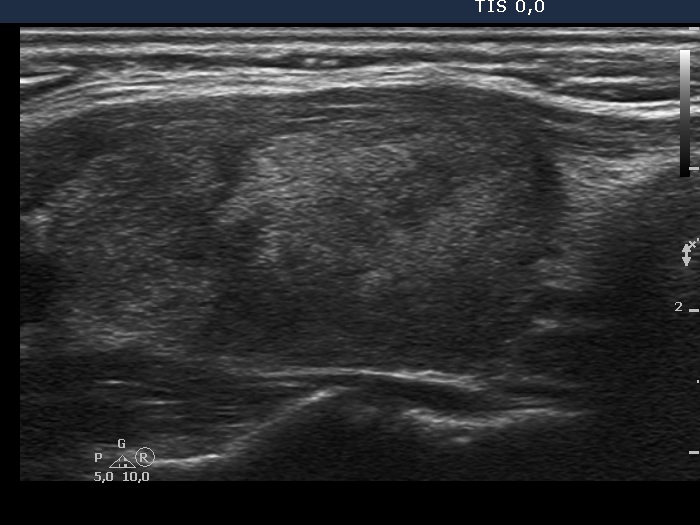

Case 374 (ultrasonographic picture 5)

Left lobe, longitudinal scan.